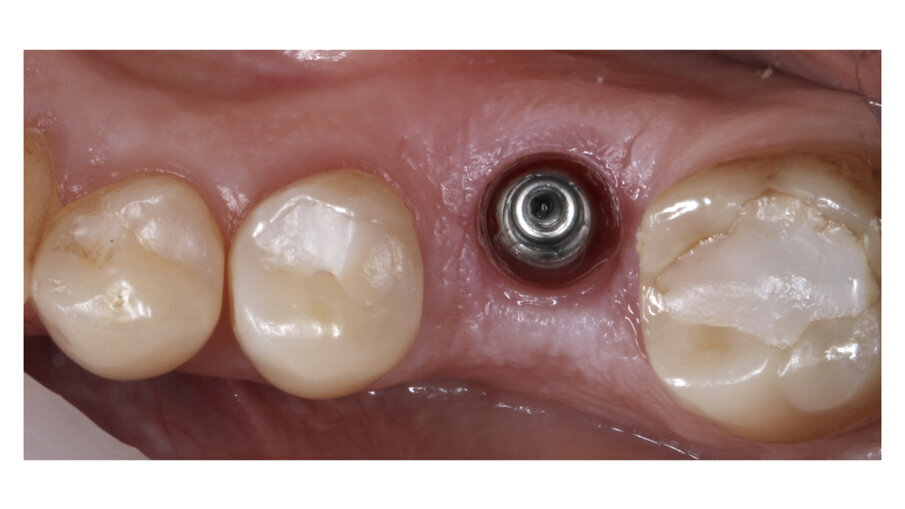

During daily practice, it is very common to face situations where the implant has to be placed lingually due to normal resorption (Fig. 1) of the buccal plate after the extraction. But, at the same time, it is not necessary to perform bone grafting procedures. The result of this scenario is to increase the stress on the implant-bone complex when we use rigid materials like conventional ceramics (Fig. 2). For this daily practice situation, the combination of rigid and resilient materials against the antagonist, allows the stress to the implant-bone complex to be reduced (Figs. 3, 4).

Fig. 1: Implant placed lingually due to the normal resorption of the buccal plate.

Fig. 2: The design of the crown has to be with a pseudo pontic, increasing the oblique load on the crown.